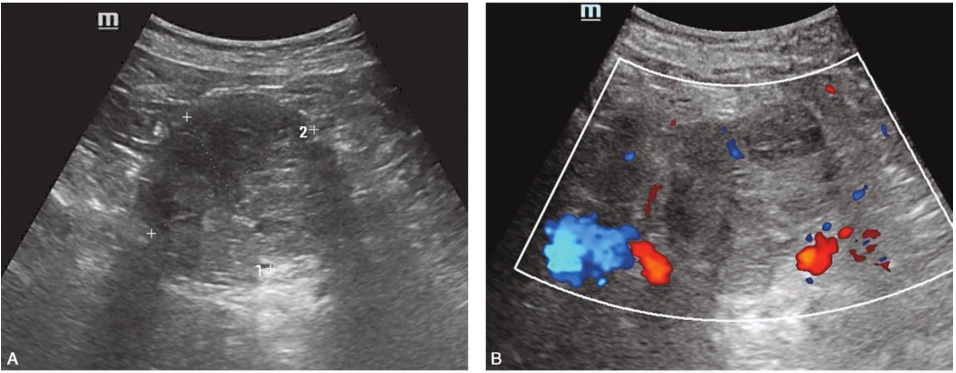

送检胰十二指肠切除术标本,胰头部可见一肿块,大小6.5cm×5cm×6cm,切面灰白灰黄,略呈囊性,内充清亮液。镜下示:大量小囊组成,囊壁被覆单层立方或扁平上皮,胞质透亮,细胞分界清晰,核深染,大小较一致,与上皮紧邻处可见明显的毛细血管网,囊腔周围为明显玻璃样变的纤维组织(图4)。本例形态典型,诊断明确为胰腺微囊型SCN。

图4 肿瘤切片HE染色(×100)

多个囊腔内衬透明的立方上皮,可见呈乳头状突向腔内,肿瘤与周围的胰腺组织分界不清。